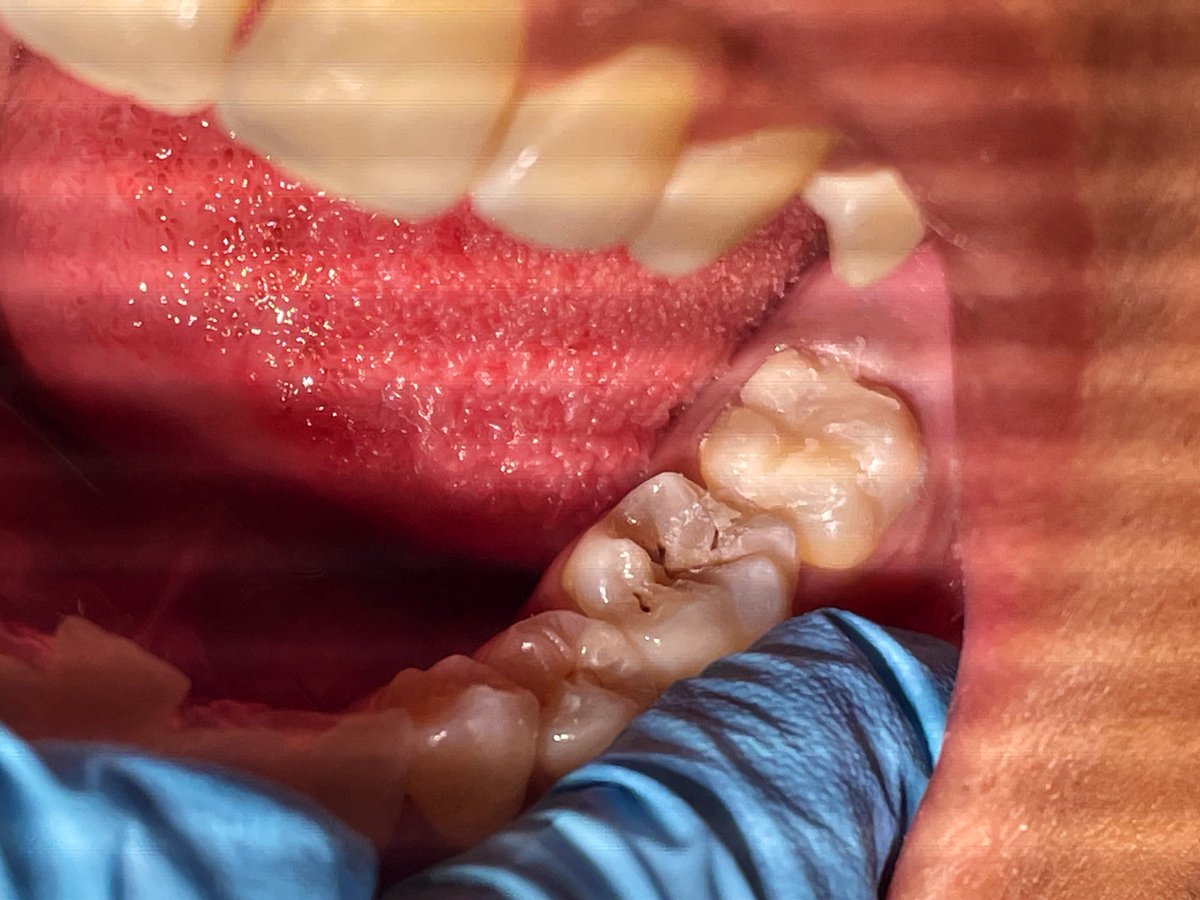

Intern Case Report – Endodontic Management of Tooth #22 with Periapical Abscess حضرت المريضة لاستكمال Endodontic treatment للسن رقم (22)، وكانت تعاني سريريًا من Periapical abscess مصحوب بأعراض ألم وتنميل. تم تحديد وتأكيد Working Length (WL) وبلغ 19.5 mm عند إجراء Canal negotiation تبيّن أن القناة Narrow canal، وعليه تم البدء بمرحلة Cleaning and Shaping باستخدام Hand files بشكل تدريجي حتى مقاس #35 بهدف إنشاء Glide Path آمن يسهّل إدخال الأدوات ويقلل من احتمالية حدوث Canal transportation أو Ledge formation أو Instrument separation. تم إجراء irrigation بصورة مستمرة خلال جميع مراحل التحضير لتعزيز Debridement وتقليل البكتيريا داخل القناة الجذرية. بعد تحقيق Preliminary enlargement مناسب، تم إدخال Rotary instrumentation ابتداءً من مقاس #20 لاستكمال Biomechanical preparation مع المحافظة على المسار التشريحي الأصلي للقناة. في نهاية الجلسة تم وضع Composite filling لضمان Coronal seal ومنع Reinfection .